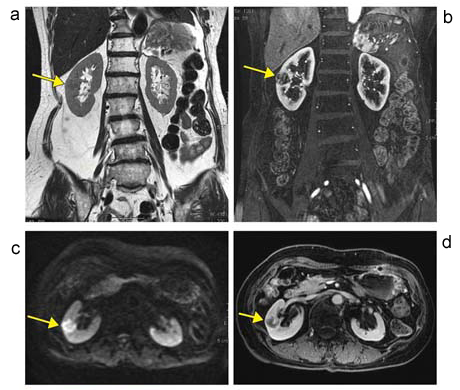

図6 直腸がん腎転移

a:呼吸停止下FSE法 T2強調画像 /

b:Gd造影ダイナミック動脈相,LAVA-FLEX Water image

c:呼吸同期 DWI(b値800) /

d:Gd造影平衡相,LAVA-FLEX Water image

T2強調画像(a)ではわずかな低信号を示す病変(→)である。Gd造影ダイナミック動脈相(b)では内部の隔壁構造に染まりが認められる。病変は,DWI(c)で高信号,Gd造影平衡相(d)では一部造影効果のある淡い低信号を示す(→)。いずれの画像でも信号の均一性は良好である。